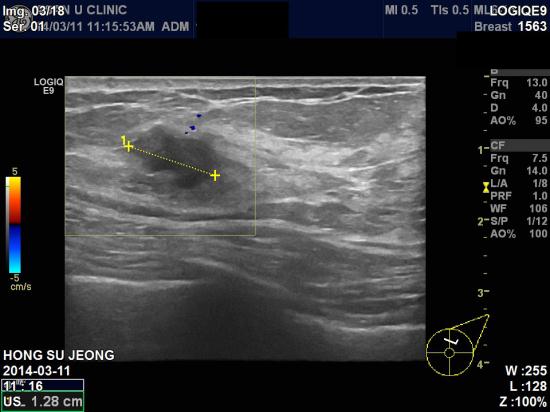

아산유외과 진료 후 72번째 유방암진단.

건강검진에서 실시한 유방암검사상 좌측유방의 이상소견을 주소로

내원하신 62세 환자분이십니다.

좌측유방 12시방향 젖꼭지에서 3cm 떨어져서 1.45 cm 결절과,

그옆으로 0.38 cm 결절 두곳 조직검사결과

1.45 cm 결절이 침윤성 유관암으로 진단되었습니다.

환자분은 만져지지 않는다고 했지만,

보통 자가검진을 열심히 하다보면 1cm 혹부터는 촉진이 가능합니다.

자가검진의 중요성이 다시한번 강조됩니다.